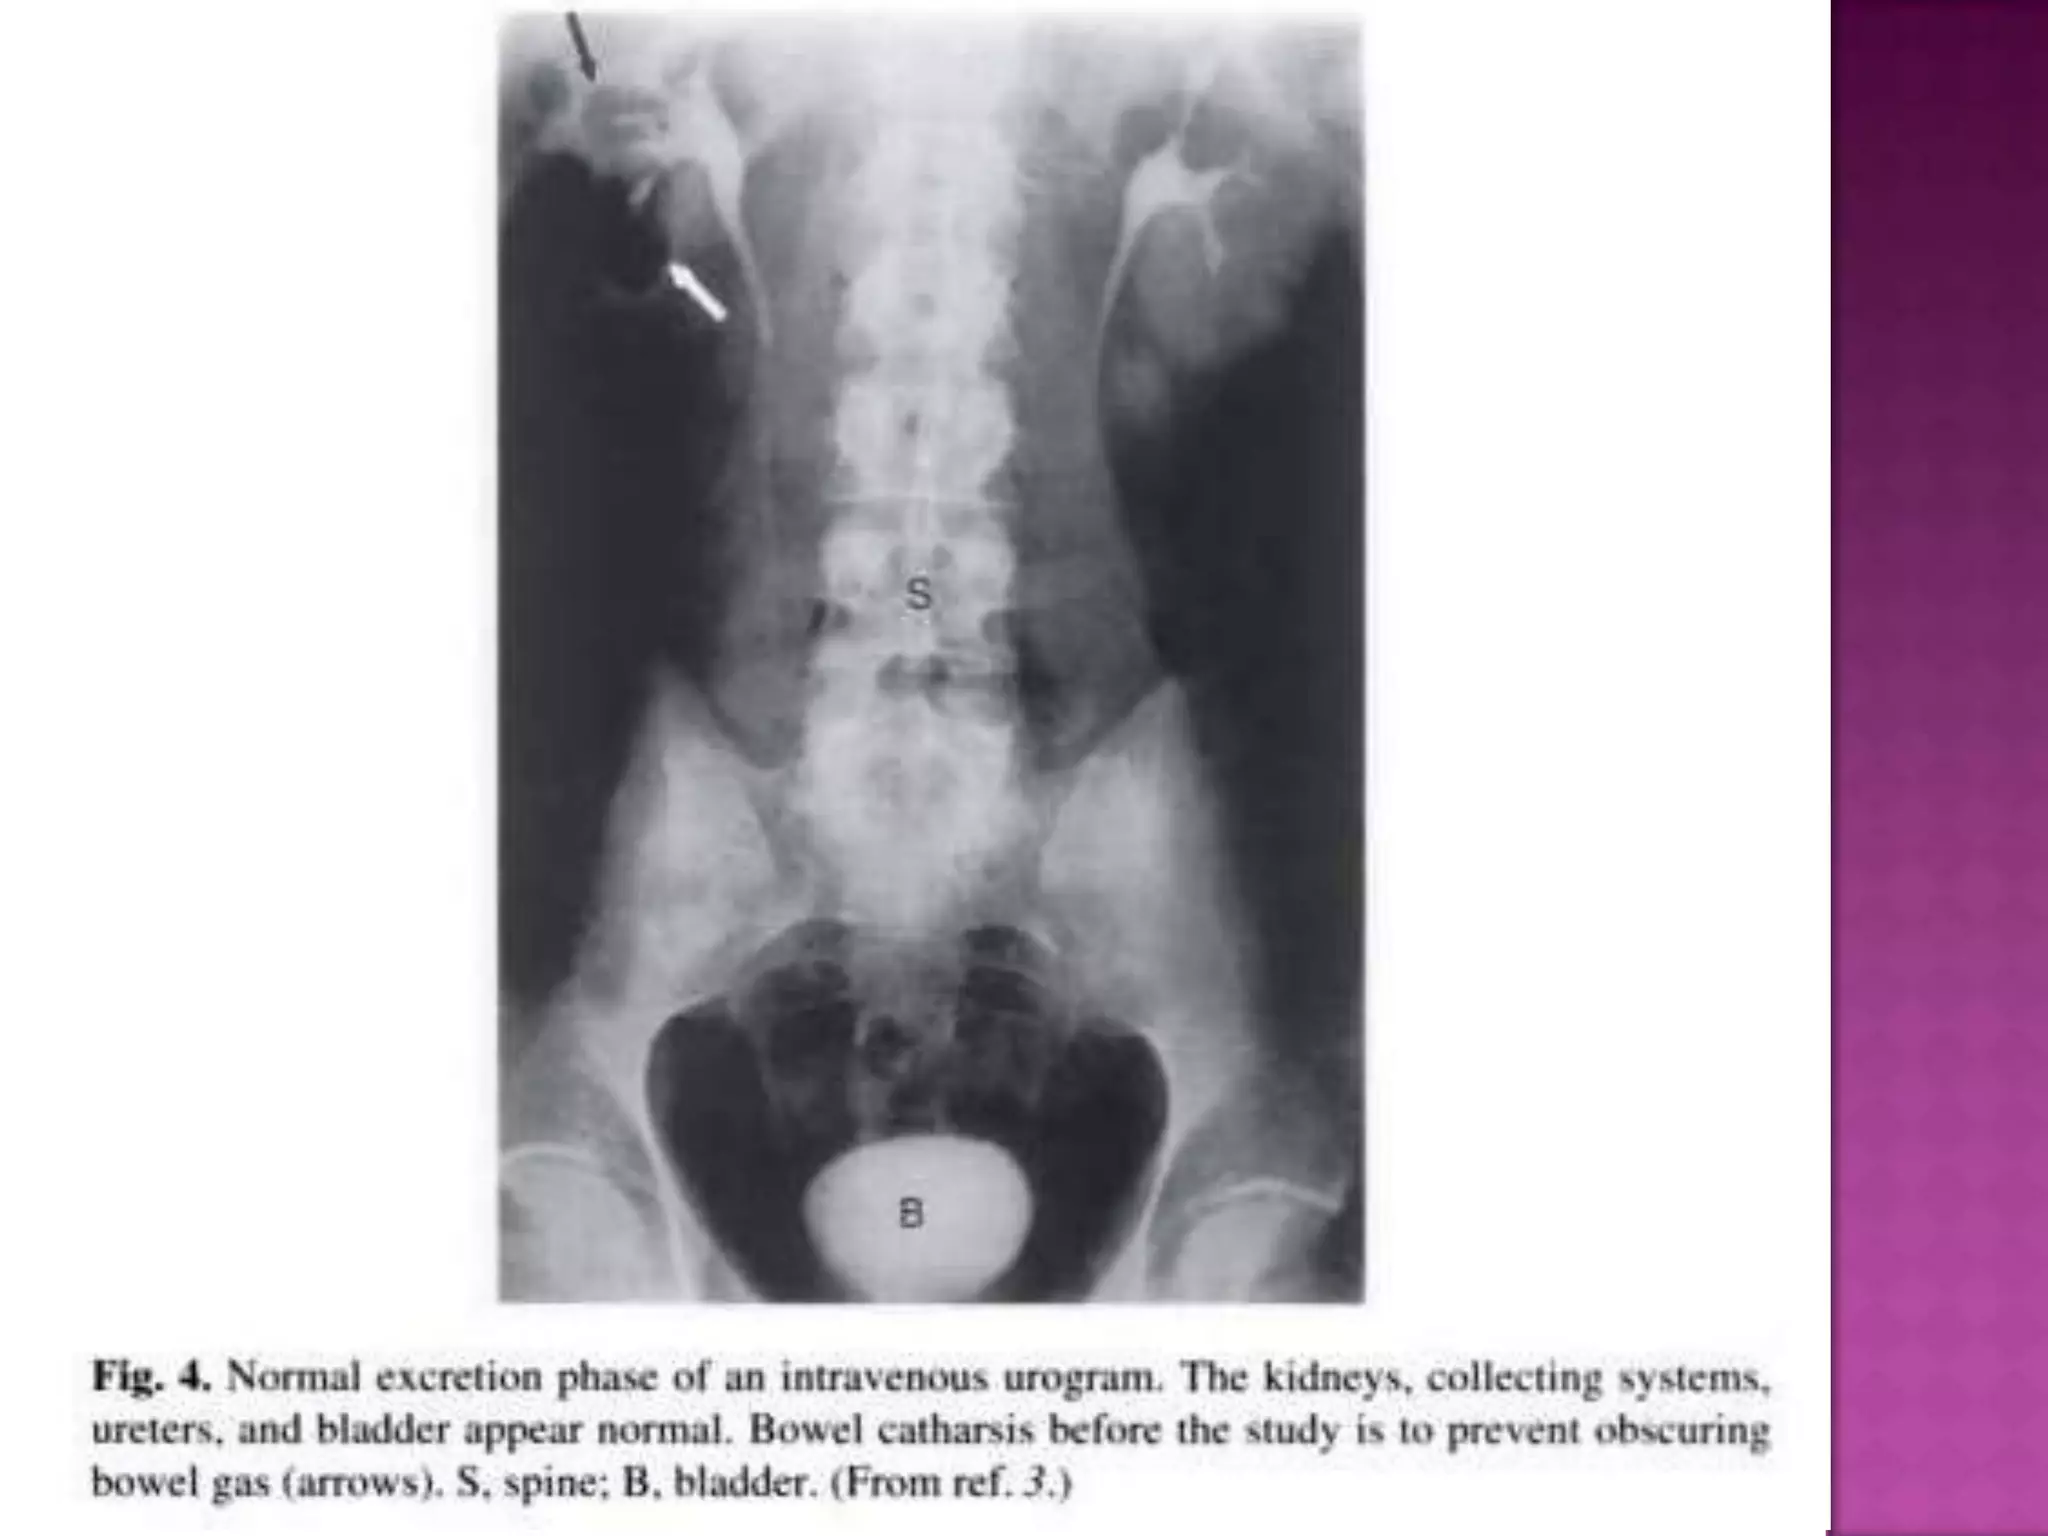

On a radiograph obtained during bladder filling, the contrast material is

smoothly defined and the bladder wall has become less evident. A normal

uterine impression on the superior margin is noted

Post Micturition film to demonstrate the bladder emptying success, and the

return of the previously distended lower ends of ureters to normal.